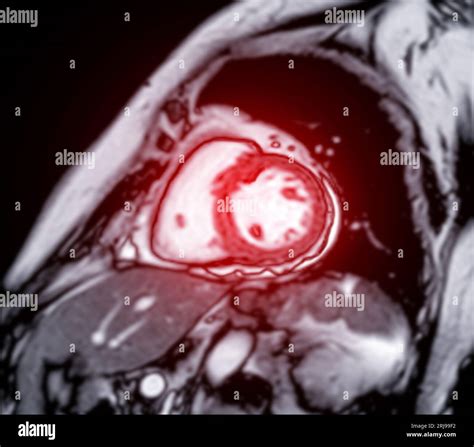

• Assessing Heart Function: MRI provides detailed information about the heart's pumping ability, ejection fraction, and wall motion. This is crucial for diagnosing and managing heart failure.

• Detecting Heart Disease: MRI can identify coronary artery disease, myocardial infarction (heart attack), and other forms of heart disease by visualizing the heart's blood vessels and tissue.

• Monitoring Heart Conditions: MRI is used to monitor the progression of heart conditions and the effectiveness of treatments over time.